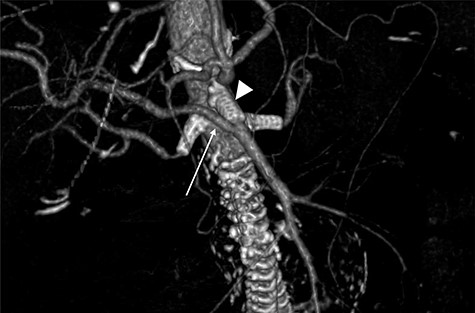

Terumo Aortic Anaconda three-vessel fenestrated and bilateral iliac branched graft was used for repair and was deployed in perirenal position with stents to the SMA and both renal arteries. Surgical arterial access was via left axillary artery (LAA) and percutaneous access was ultrasound-guided via common femoral arteries (CFA) bilaterally. Cannulation of left renal artery (V12 5 × 22 mm) and SMA (V12 9 × 32 mm) was via CFA and right renal artery (V12 5 × 22 mm) was through LAA. There was intra-operative difficulty in SMA cannulation, which was eventually cannulated after repositioning of graft (Fig. 3). Final intra-operative angiogram showed patent renal arteries bilaterally, SMA and common iliac arteries bilaterally (Fig. 4). Post-operatively, he was transferred to surgical high dependency unit (HDU). Three days post FEVAR, he developed abdominal pain, haematemesis and melaena with significantly raised inflammatory markers. CT mesenteric angiogram showed an ischaemic small bowel segment. A necrotic gallbladder was found incidentally during laparotomy, which required cholecystectomy after 20 cm segment of small bowel had been resected and decision was made to not anastomose the small bowel due to the intra-operative findings. A relook laparotomy was performed for small bowel anastomosis and drainage of bile collection found in the gallbladder fossa. Histology results later confirmed infarcted gallbladder with extensive acute inflammation as well as congested, ischaemic and focally infarcted small bowel segment with peritonitis.

Mid-implantation angiogram showing both renal stents deployed (arrowheads) and SMA cannulated (arrow).

Follow-up CTA showing all visceral stents patent and RRHA (arrow) from SMA (arrowhead).